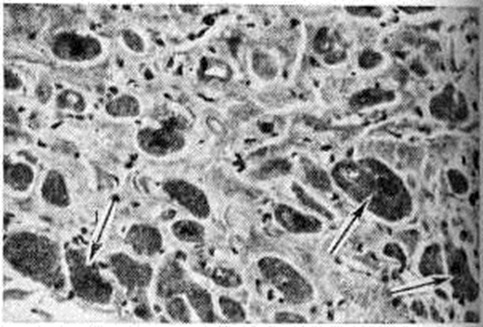

В заключительной стадии поражены обширные участки миокарда обоих желудочков, особенно — левого. В основном выявляются дистрофические и некротические изменения миокардиоцитов, начиная от вакуолизации перинуклеарной зоны цитоплазмы (смотри полный свод знаний Вакуолизация) и до цитолиза (рисунок 2) с полным растворением тел клеток (смотри полный свод знаний Цитолиз). От клеток остаются только следы в виде мелких зёрен липофусцина. В результате образуются ареактивные участки депаренхимизации миокарда (рисунок 3) с так называемой пустой сеткой, в дальнейшем замещаемые соединительной тканью. Ряд мышечных волокон подвергается мелкоглыбчатому и мелкозернистому распаду с образованием фуксинофильного детрита, резорбция которого также заканчивается миофиброзом. Процесс вакуолизации и лизиса распространяется и на клетки эндотелия кровеносных сосудов в очагах поражения. Процесс в целом напоминает дистрофический (деструктивный) миокардит. Нередко обнаруживаются также воспалительные лимфогистиоцитарные инфильтраты с примесью сегментоядерных лейкоцитов; в сочетании с дистрофическими изменениями создаётся картина смешанной формы идиопатического (аллергического) миокардита. Внутриорганные мелкие артерии и артериолы изменяются по типу аллергического васкулита (смотри полный свод знаний) — от фибриноидного некроза стенки (рисунок 4) до облитерирующего панваскулита. Все эти процессы обнаруживаются на фоне распространённых полей кардиосклероза различной зрелости (рисунок 5), подобно миокардитическому кардиосклерозу (смотри полный свод знаний Кардиосклероз), что свидетельствует о прогрессирующем и длительном течении поражения миокарда. В дистрофический и рубцовый процессы вовлечены и различные отделы проводящей системы с миоцитолизом (рисунок 6).

Рис. 4. | ||